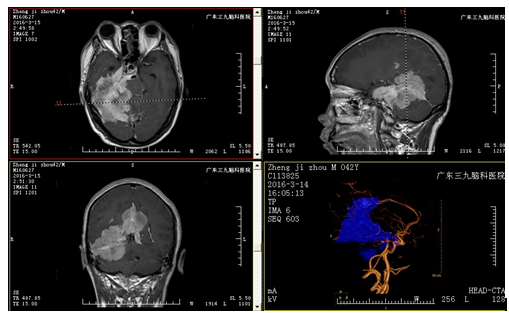

郑男子,42岁,头痛头晕1年余,加重伴行走不稳及视力下降2月,在当地院医院行MR示:右侧颞枕部、小脑、胼胝体及右侧桥小脑区占位性病变。为求进一步有效治疗,来我院就诊。

入院后完善相关检查,复查头颅MRI示:1.右侧中后颅窝及大脑镰后部脑外及部分脑内占位病变,累及桥前池及右侧内听道、右侧海绵窦区,考虑肿瘤性病变,全脑血管造影示:右侧中后颅窝占位性病变异常染色,提示血供丰富,考虑窦组织细胞增生症(RDD)或不典型脑膜瘤可能;2.右侧大脑镰下疝;小脑扁桃体下疝;完善术前准备后,行全麻下中后颅窝幕上幕下占位性切除术,手术由神经外二科主任林涛主刀完成,手术顺利,术后安返病房,予营养支持、抗炎、营养神经、预防癫痫、保护胃肠道、脱水等治疗。术后复查头颅CT、MRI示:呈术后改变,肿瘤大部分切除。术后病理结果回报:不典型脑膜瘤。